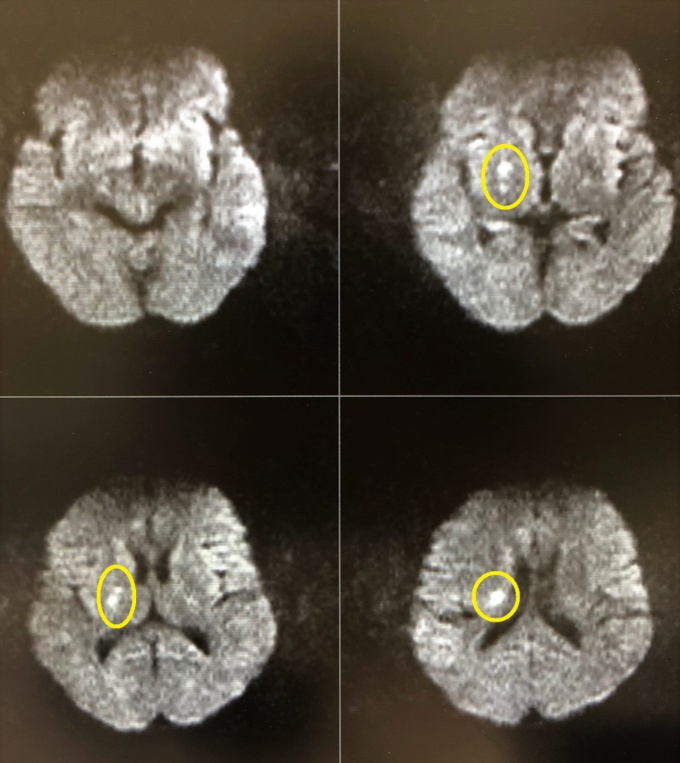

昨日、受診された50歳代の女性の患者さんです。2~3日前から、軽いめまいとしゃべりにくさを自覚していました。様子をみるも改善せず、当院を受診されました。診察所見では、軽いめまいとしゃべりにくさのみでした。頭部MRIを施行して急性期の脳梗塞を認め、すぐに総合病院に紹介しました。

黄色でマークした箇所が脳梗塞の部位です。